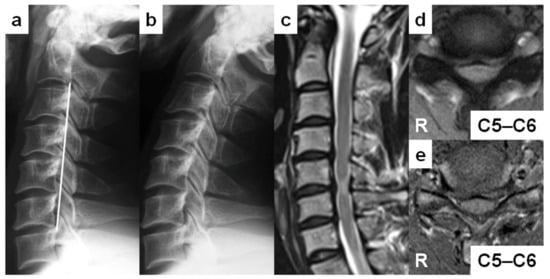

| 1 | 27 | Man | 0.5 | Judo | Postman | − | C5–C6 | 14 | + | 17 |

| 2 | 28 | Man | 0.5 | Judo | Police officer | − | C5–C6 | 13 | − | 13 |

| 1 | Straight | + | C3, C4, C5, C6, C7 | + | C4, C5, C6, C7 | + | C5–C6 | − | |||

| 2 | Straight | + | C3, C4, C5, C6, C7 | + | C4, C5, C6 | + | C5–C6 | − | |||

| 1 | + | C3–C4, C4–C5, C5–C6, C6–C7 | + | C4–C5, C5–C6, C6–C7 | + | C5–C6 | Angular edged |

| 2 | + | C2–C3, C3–C4, C4–C5, C5–C6, C6–C7 | + | C4–C5, C5–C6, C6–C7 | + | C5–C6 | Angular edged |